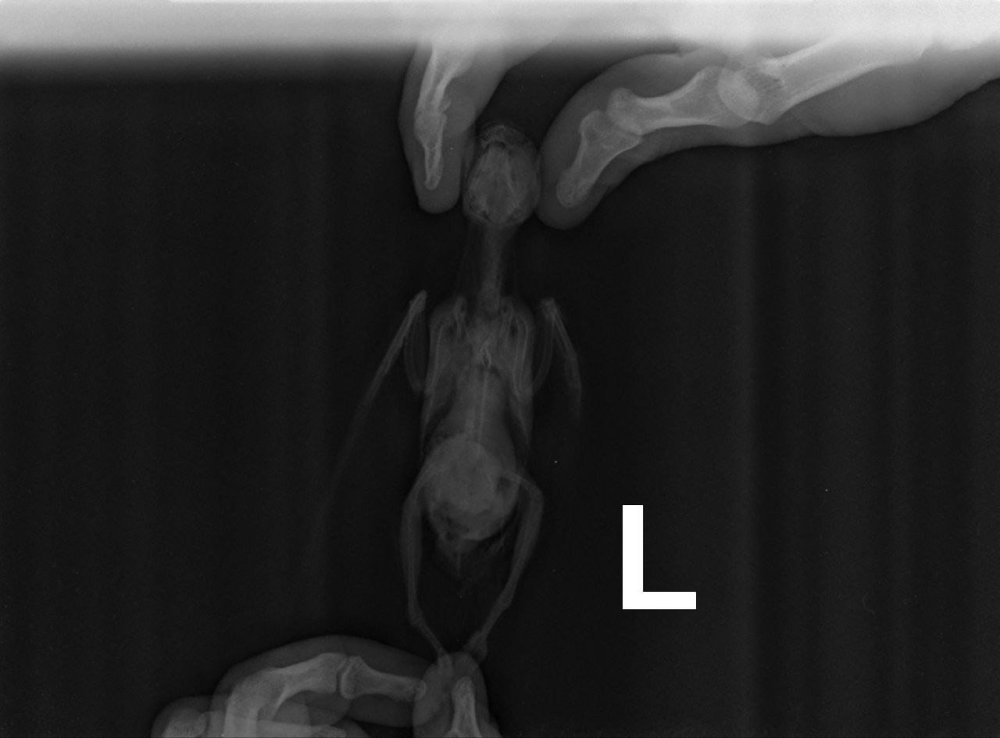

Когда я его нашла он весил 147гр. выглядел не очень, но всегда активничал даже тогда, очень любознательный птенец Сейчас выглядит так. Фото прилагаю ) Рахита не было. Держит координацию и стоит на лапках хорошо, только вот шишка на лапке внесла свои коррективы на время. С момента как я его нашла я давала им обоим и Сумамед (птенцу 3 недели, взрослому 6 недель - болел до появления птенца воспалением легких, а может кстати и нет) и Азитромицин давала обоим дней 10 точно. Плюс птенцу делали блокаду на ножке цефтриаксон (тоже антибиотик) и сейчас еще 6 недель!? Может есть какие уколы? Они не умрут от антибиотиков???

расскажите пожалуйста про дозировки а срок 15 дней недостаточен поскольку у нас нет анализа с результатом "микоплазмоз - отрицательно" поскольку голубь кормил малыша из клюва то да нужно как сейчас весит и выглядит малыш? рахита у него не было? при лечении доксициклином малыши плохо растут так как доксициклин НЕ совместим с кальцием очень неплохо! вес дикого сизарика обычно 250-300 грамм (320 грамм бывают хорошо откормленные крупные самцы) потому при таком весе доксицклин на росте не скажется скорее всего он проглотит но может и откашлянуть и выплюнуть отвар крапивы или подорожника нужен заранее улучшить сворачиваемость крови чтобы нарост по возможности отвалился бескровно если нарост на кости или на корне языка бывает что отваливается вместе с челюстью или с языком потому заранее проверить (в этом случае подключают антибиотик от некроза) ещё бывает ужас когда нарост на пищеводе вдоль шеи а вот на зобу выглядит страшно гораздо безопаснее и хорошо заживает тема про трихомоноз https://www.mybirds.ru/forums/topic/65174-trihomonoz/

Ну т.е. все что назначено даю. И птенцу тоже? Это куплю завтра тогда еще. Вес птенца 275гр Вес взрослого 330гр Это тоже завтра начну давать. но у меня вопрос. А как он отвалится, если это внутри? Он не задохнется? Как это отторгается?